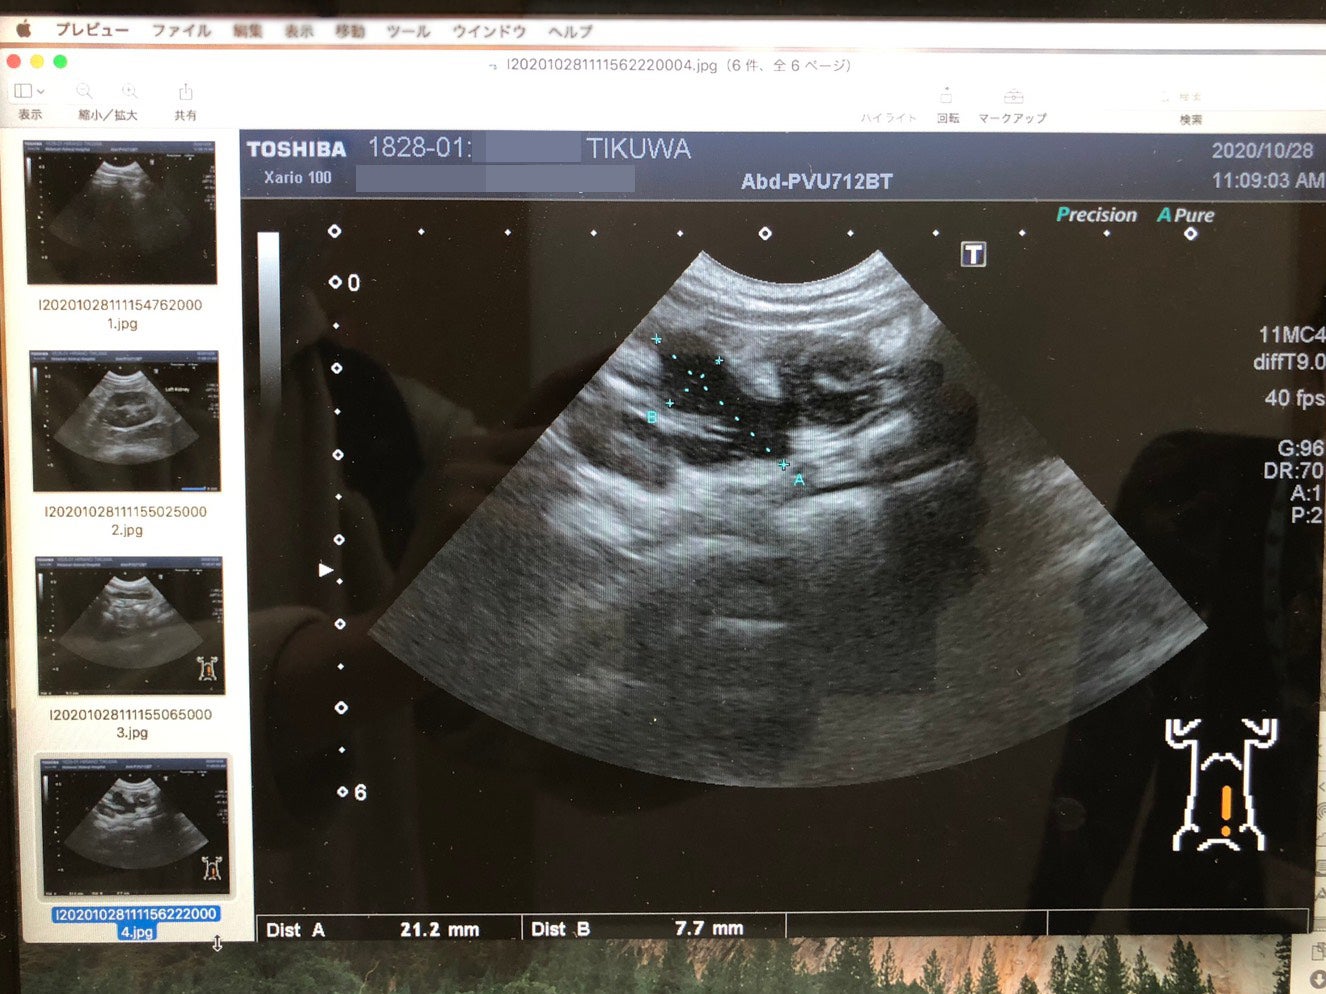

10月20日、動物病院に連れていき血液検査とエコーによる検査をすると、 血液検査で異常があり、腸管に炎症症状がみられることが発覚しました。

血液検査で、高グロブリン血症と肝疾患が確認されました。また、エコー検査で腸管の炎症が見られました。この結果を受けて、すぐに採取した血液をFIPの検査に出しました。

Mutianを処方していただける病院を見つけたので、急遽予約を取りその病院へ行きました。

そして、この日行って頂いた検査の結果、肉芽腫の発見により「ドライタイプ」であるという事が分かりました。

また、貧血が進んでいることからFIPの中期であると告げられました。